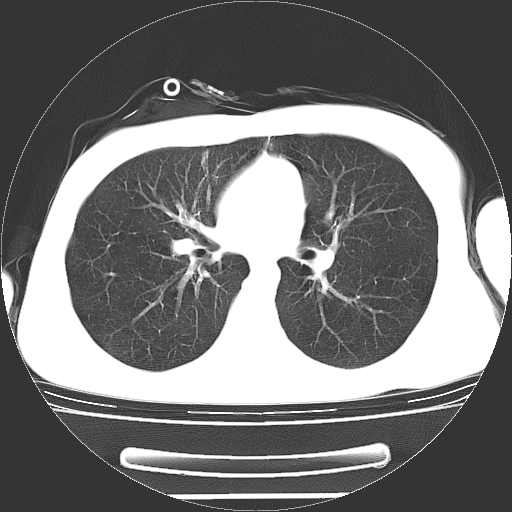

男,20岁,右侧气胸行闭式引流术后五天ct检查看肺内是否有肺大泡,纵隔窗未见异常,未上传。

未见肺大泡影

右肺未见确切肺大泡。

1)右侧胸腔闭式引流术后导管留置。2)右肺未见肺大泡。

未见肺大泡,还有微量气体。